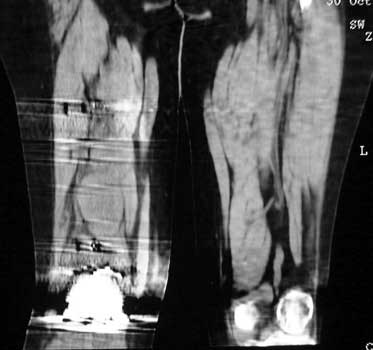

Femoral version measure by CT. Axial images are obtained through the hips and femoral condyles. A reference line is drawn through the posterior aspect of the medial and femoral condyles (Fig A). A second line in drawn through the axis of the neck of the femoral prosthesis. These lines are superimposed, and the femoral version angle is measured. (Fig B)